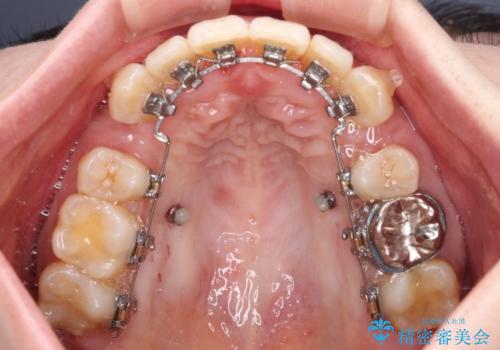

- ハーフリンガル

上顎は左右の第一小臼歯2本を、下顎は左右の第二小臼歯2本を抜歯して、口元が突出しないようにしながら、奥歯の咬み合わせを改善していく治療計画としました。

目立たない装置が希望であったため、上顎が裏側装置である、ハーフリンガル装置を選択されました。

第二小臼歯抜歯としたため、治療期間は長くなりましたが、満足のいく仕上がりとなりました。